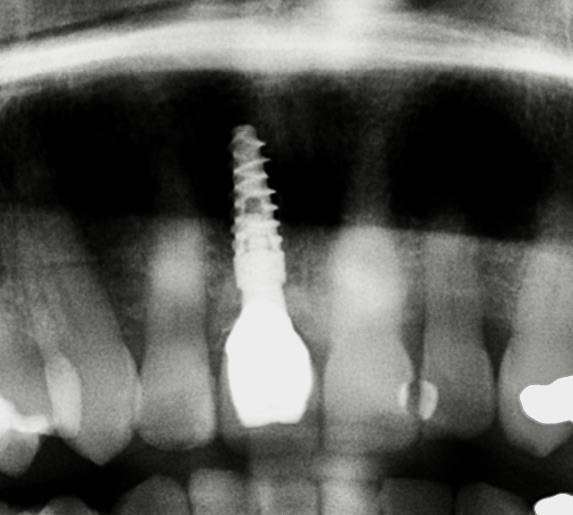

Mithilfe moderner Diagnostik, mikrochirurgischer Techniken und gewebeschonender Verfahren schaffen wir optimale Voraussetzungen für eine sichere Einheilung. Bei Bedarf werden knochenaufbauende Maßnahmen und biologische Regenerationskonzepte integriert, um auch in anspruchsvollen Situationen stabile Ergebnisse zu erzielen.